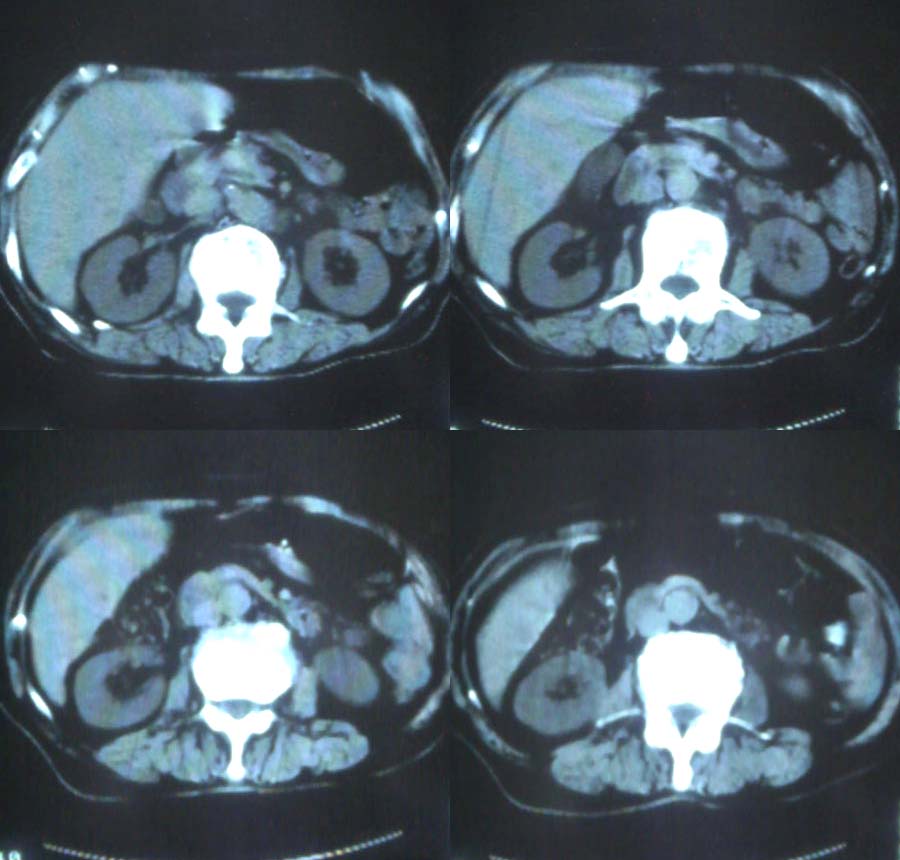

1、分析:(1)女性75岁;(2)单侧大量胸腔积液;(3)右侧肺门区团块影,单纯的压迫性肺不张?肿块?;(4)肝脏内多发结节影,大小不等,多结节型肝癌?肝癌并肝脏内转移?(5)肝脏内结节病灶中心有更低密度区;(6)右侧肾上腺不规则软组织灶;(7)肝脏各叶比例正常,脾脏不大。

肝脏和肾上腺转移瘤的诊断没问题,是不是肺癌转移很难说,没看见明确的肿块,胸部的片子太少了。

胆囊在哪?

右下叶肝脏及右肾上腺占位,右侧大量胸腔积液伴下叶肺不张,原发部位病灶不能定。也许肝右叶为原发,也未一定。